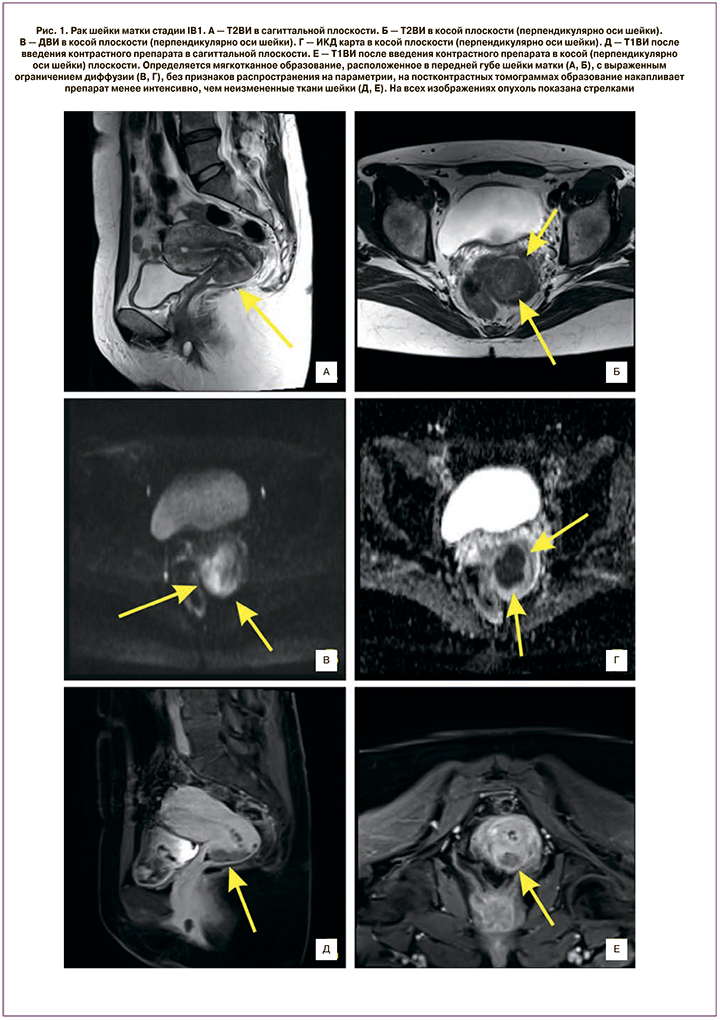

До начала специального лечения, а также на всех его этапах выполняли обследование пациенток с использованием общеклинических методов диагностики и МРТ. Мультипараметрическое МРТ включало в себя получение Т1-взвешенных изображений (Т1ВИ), Т2ВИ, диффузионно-взвешенных изображений (ДВИ), а также динамическое контрастное усиление. Инфильтрацию параметриев устанавливали по распространению опухолевой ткани за пределы шейки матки на ДВИ и постконтрастных томограммах.

При МРТ-исследовании до начала специального лечения объемы новообразований при IB2 и IIA2 стадиях РШМ составили от 3,0 до 73,3 см3 (36,6 (17,0) см3), при стадии IIB – от 32,2 до 103,1 см3 (64,9 (19,9) см3), при IIIB стадии – от 32,2 до 145,1 см3 (72,3 (23,6) см3) (рис. 1).